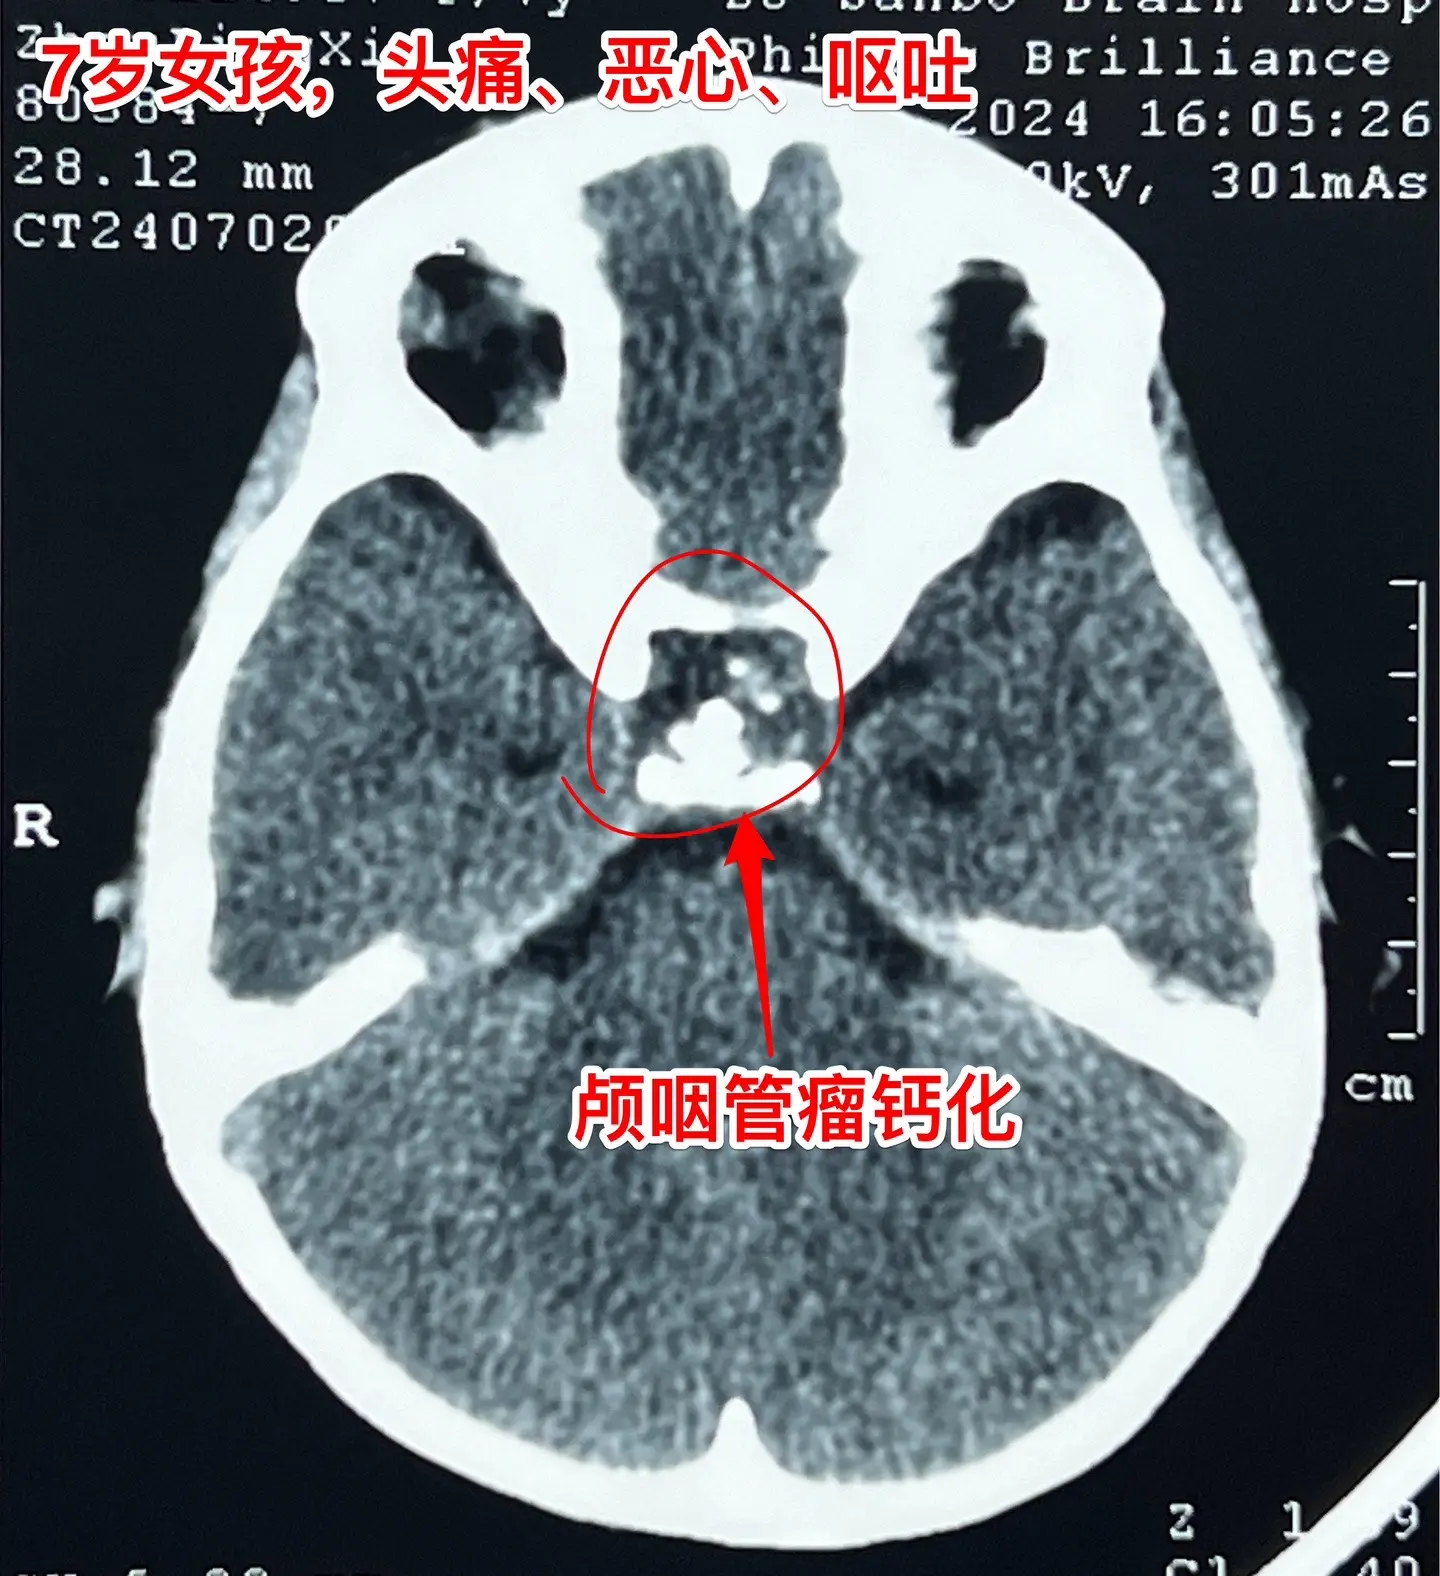

头痛、恶心、呕吐,是颅内高压症状!7岁江西上饶的小女孩,一个月前感头痛、恶心、呕吐。这是颅内高压的症状。他们到就近的医院就诊,作头部CT和磁共振,发现了颅咽管瘤,这个颅咽管瘤造成了梗阻性脑积水,颅内高压,所以小孩子出现头痛、呕吐症状。 根据头CT可以看见肿瘤内有钙化,可以确诊是典型的造釉细胞性颅咽管瘤。这样的肿瘤造成的脑积水,一般在切除肿瘤后就可以自愈,不需要专门作脑积水的手术。 2024年7月12日作了手术,肿瘤得到完全切除。 目前小孩子身体状况很好,快要出院了。